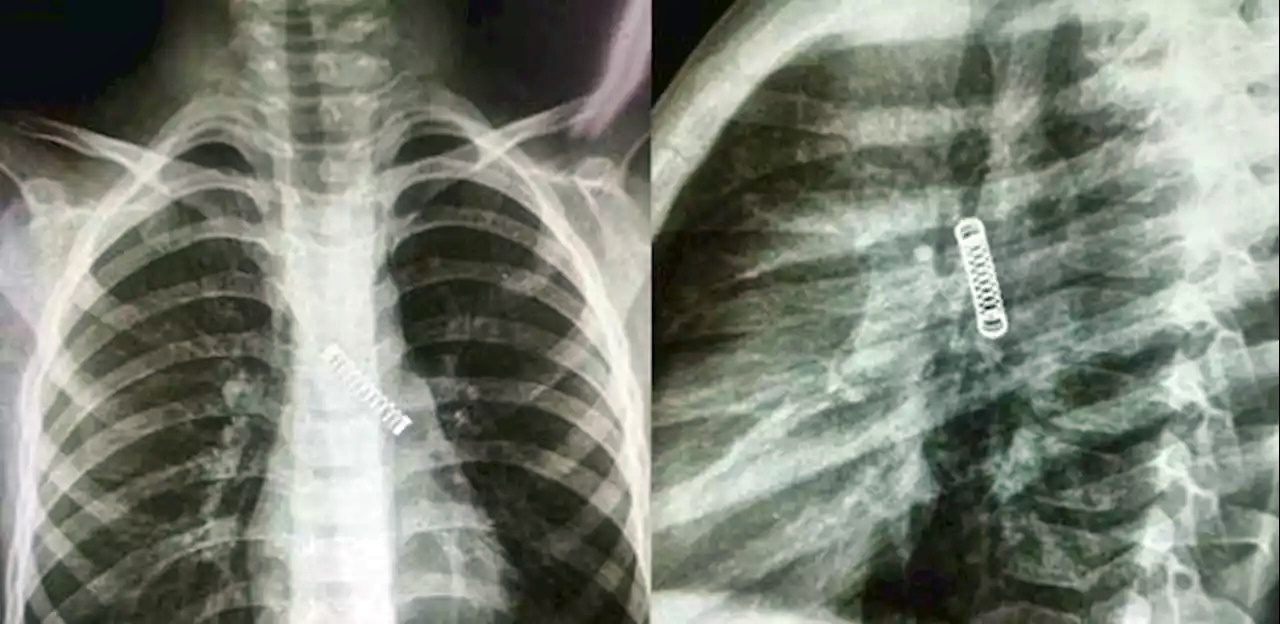

O menino foi submetido a um raio-X e os médicos ficaram surpresos ao encontrar um objeto de metal em seu pulmão esquerdo.

Um menino de 5 anos teve uma mola de metal removida de seu pulmão, depois do objeto ficar preso lá por três meses. O paraguaio de cinco anos sofria de uma tosse constante.

O menino agora está em condição estável depois que os médicos removeram com sucesso a mola em 8 de março.